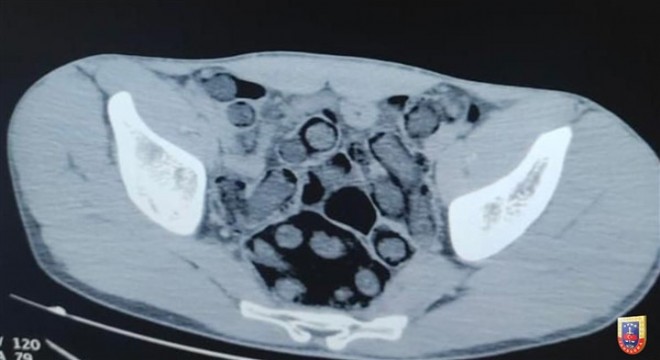

Jandarma Genel Komautanlığından yapılan açıklamada, ''Bitlis İl Jandarma Komutanlığınca yapılan istihbari çalışmalar neticesinde gerçekleştirilen operasyonda, mide ve bağırsaklarında 176 kapsül halinde 1 kilo 96 gram eroin maddesi taşıdığı tespit edilen 2 şüpheli yakalanmış, şüpheliler sevk edildikleri mahkeme tarafından tutuklanmıştır.'' denildi.